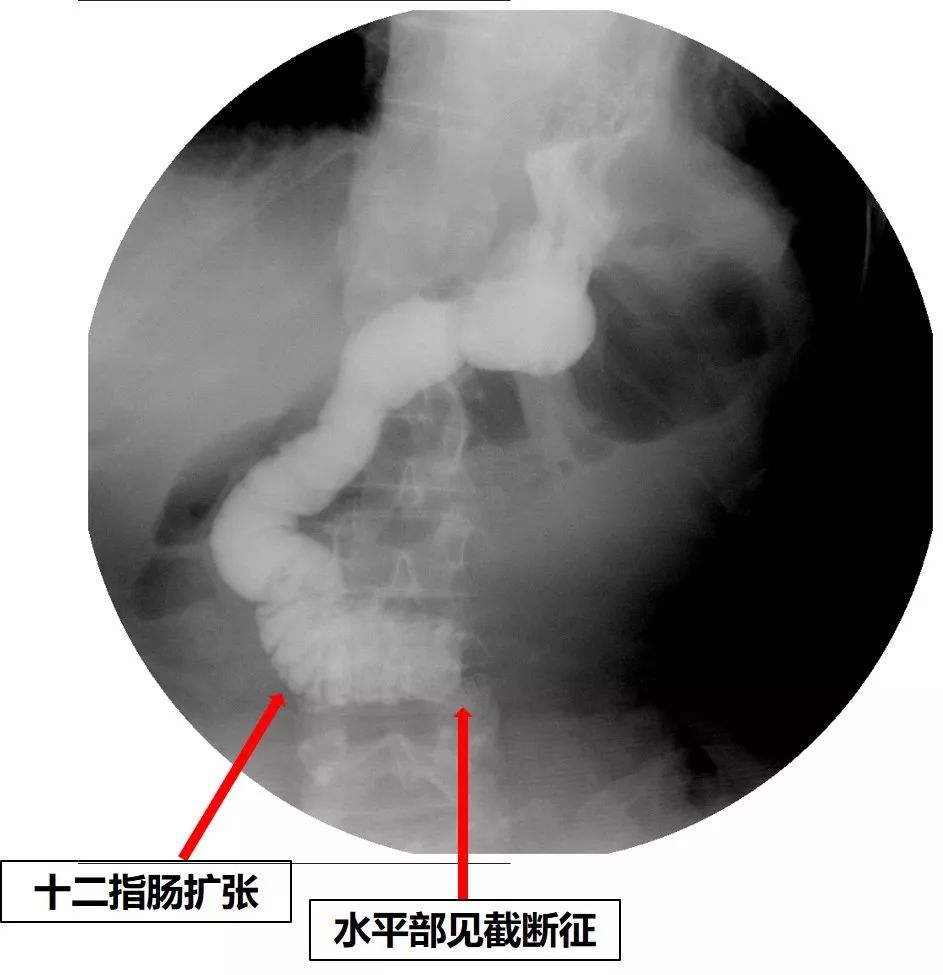

到此为止,患者已经接受了3次大的腹部手术,并接受了放化疗。但是,疾病仍然进展。2018年6月下旬患者出现恶心、呕吐,腹痛、腹胀,不能进食,X线腹部平片及腹部CT检查提示肠梗阻合并感染(见图1、图2),给予抗炎对症治疗效果差。结肠镜检查见横结肠占位伴梗阻(图3)。患者腹痛腹胀进行性加重,出现高热、血压下降等感染性休克症状。患者已经无法耐受再次开腹手术!

图1 腹部X线平片见扩张的肠管和气液平——典型的肠梗阻

图2 腹部CT可见扩张的肠管和气液平